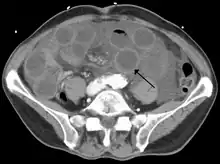

Computed tomography (CT) showing dilated loops of small bowel with thickened walls (black arrow), findings characteristic of ischemic bowel due to thrombosis of the superior mesenteric vein.